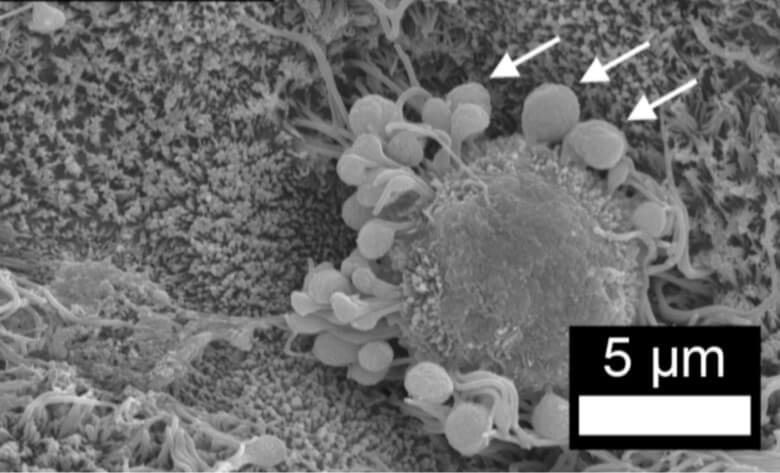

– Glándulas merocrinas: estas liberan sus productos mediante exocitosis (como la glándula parótida), por lo que en dicho proceso no participan ni el citosol ni la membrana plasmática.

– Glándulas apocrinas: son aquellas glándulas cuyas células liberan parte de su contenido citosólico con cada secreción (ejemplo son las glándulas mamarias).

– Glándulas exocrinas multicelulares: su estructura está conformada por “racimos” de células secretoras que pueden estar “acomodadas” u organizadas de distintas maneras. Puesto que son muchas células en constante contacto y comunicación, estas se comportan como un órgano de secreción.